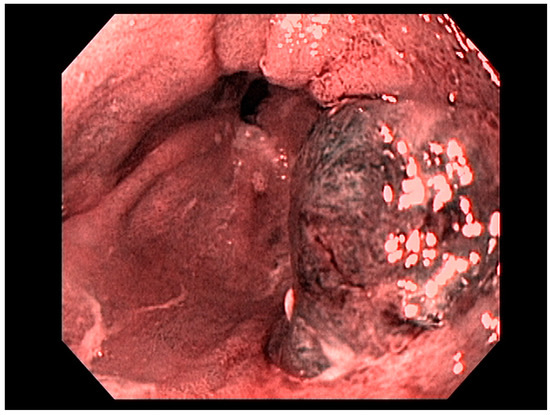

4. Gastric Malignancies

4.1. Gastric Adenocarcinoma

4.2. Early Gastric Cancer (EGC)

4.8. Treatment